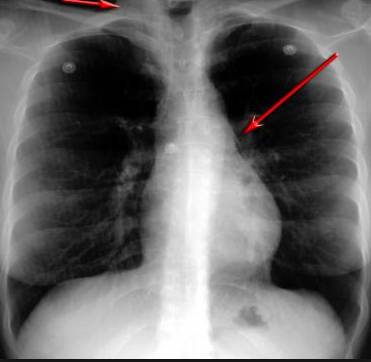

并且,因?yàn)楹粑到y(tǒng)結(jié)構(gòu)復(fù)雜,在體檢時(shí)醫(yī)生很難通過一種檢測(cè)手段,判定早期患者的病情。

使用這臺(tái)掃描儀,將直接把器官變成3D圖形!細(xì)微的毛細(xì)血管,幾毫米大的肺泡和支氣管,都將能看的一清二楚!

你的每一個(gè)氣泡,每一段支氣管,哪兒有病變都清清楚楚的將展示在醫(yī)生面前!

也就是說在一切都還沒開始惡化前,把這些有問題的器官組織都暴露的一清二楚:

這臺(tái)儀器不僅僅是一臺(tái)能拯救幾百萬條生命的高清掃描儀,它更是一場(chǎng)開天辟地的技術(shù)革新!因?yàn)樗粌H能幫醫(yī)生看到肺病的結(jié)構(gòu)圖,

還能看到器官是如何運(yùn)動(dòng)的!

空氣是如何進(jìn)入到肺部,氧氣是如何到血液,任何微小的變化都將曝露在醫(yī)生面前!更清晰的圖像,更細(xì)節(jié)的變化!

不同于CT掃描,需要從同一角度,拍下無數(shù)張器官二維圖,從而搭建3D器官結(jié)構(gòu)圖那般費(fèi)時(shí)費(fèi)力。

4D掃描儀將直接從不同角度,同時(shí)對(duì)人體器官進(jìn)行掃描,然后通過計(jì)算機(jī)算法進(jìn)行快速成像。CT需要花幾小時(shí)才能完成的工作,

4D掃描將在幾秒內(nèi)完成!

當(dāng)大家還在為B超、X光、CT哪個(gè)輻射更少而爭(zhēng)論不休時(shí),這臺(tái)新機(jī)器已經(jīng)比現(xiàn)有掃描儀少20%的輻射

不需要重復(fù)拍片,輻射也更少!

沒有這項(xiàng)新技術(shù),醫(yī)生在做體檢的時(shí)候,很難通過一種測(cè)試斷定一個(gè)人是否有呼吸系統(tǒng)疾病。

可是現(xiàn)在他們不但能看到整個(gè)肺部的3維結(jié)構(gòu)圖。還能看到空氣進(jìn)入人體后的所有微小變動(dòng)!